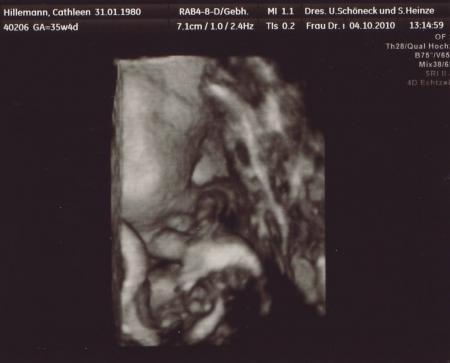

so, jetzt möchte ich auch mal wieder Bilder von meiner Maus zeigen - in 3D und es gab sogar ein Video sie ist knapp zeitgerecht entwickelt, ist halt immernoch ne zarte BPD 89,0 mm FOD 108,5 mm KU 311,4 mm AU 292,0 mm FL 68,1 mm geschätztes Gewicht bei 35+4: 2292 g

Bild zu Bilder vom Zusatz-Ultraschall - Forum für November - Mamis